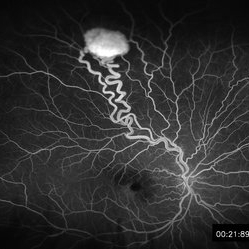

Retinal Hemangioblastoma early FA

May 15 2013 by Robert T. Wendel, MD

20-year-old male. Genetic hx not yet defined.

Condition/keywords: Von Hippel-Lindau

Retinal Hemangioblastoma Mid Phase FA